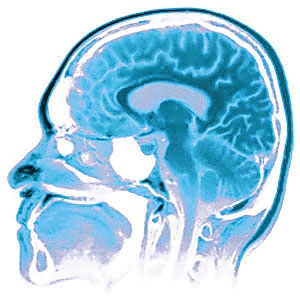

福氏纳格里阿米巴原虫喜热、喜潮湿,主要生存于江河、池塘、水坑中,甚至在热水和潮湿的泥土中也可能找到它们的踪影。在水中,它们主要以滋养体的形态生活,有时会长出长长的鞭毛,有时又伸出形态不同的手足,运动十分活跃。当遇到人后,它先进入人的鼻腔,再穿过鼻黏膜,沿着嗅神经钻入人脑。所以,得病的人大都会游泳,在患病前多有在不干净水中游泳的历史,有时也可能是用河水洗头、洗脸而感染的。

福氏纳格里阿米巴原虫钻进人脑后,可以迅速繁殖,然后沿着脑膜向脑中心部位播散,引起化脓性脑膜脑炎、血管出血和脑实质坏死。由于福氏纳格里阿米巴原虫在自然界以吃细菌或其他微生物为生,它们体内经常寄生着许多细菌,因此还有可能把细菌带进脑子里,引起细菌性炎症。所以说所谓福氏纳格里阿米巴原虫能 “吃”人脑,其实是指原虫进入人脑后引起的脑组织炎症和破坏,并非真的“食脑”。